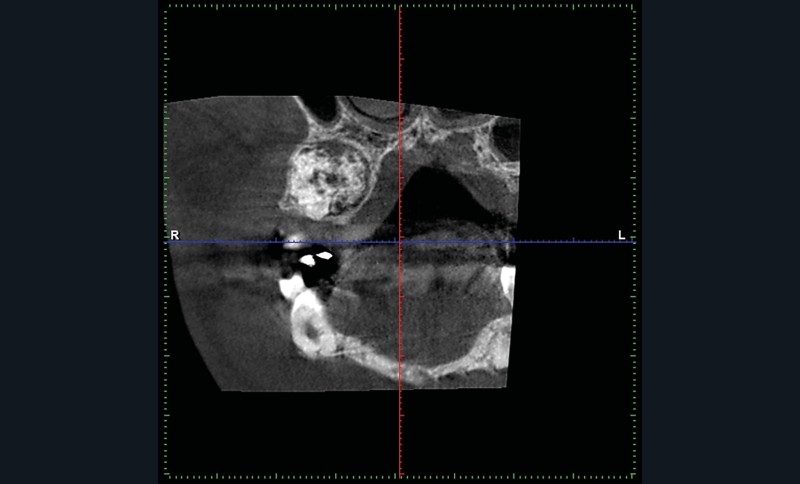

Un CBCT est pratiqué : la périphérie de la lésion ne présente pas de réaction ostéoclérotique (fig. 2) et on retrouve un liseré radioclair « ceinturant » la lésion (fig. 3).